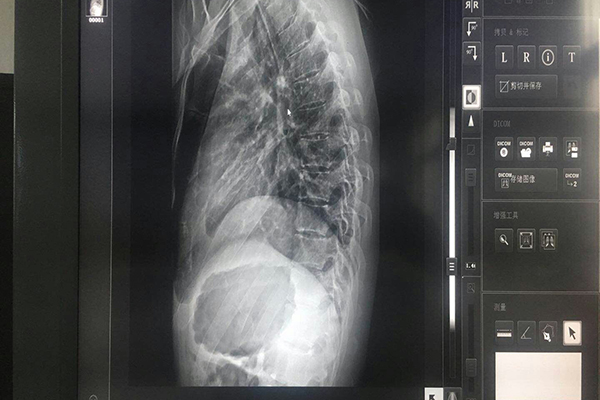

為了使放射學(xué)界對數(shù)字影像系統(tǒng)的診斷準(zhǔn)確性問題有充分的認(rèn)識,了解醫(yī)用顯示器在數(shù)字影像中的作用.顯示器i中灰階是什么?灰階是指顯示器顯示從亮值到黑值之間所能夠顯示的層次。灰階是真實顯示醫(yī)學(xué)圖像中患者病灶的一個重要參數(shù),只有灰階的層次多,才能夠保證較高的讀片質(zhì)量。普通顯示器有8bit-?256灰階,用于顯示彩色的圖象,無灰階要求;醫(yī)用顯示器有10?bit-1024灰階,用于顯示X光灰階圖象,于診斷相關(guān)。

人眼對灰階的分辨能力使隨著亮度的不同,有著一個非線性關(guān)系。亮度越高,人眼能辨的灰階就越多。反之,低亮度時,人眼對灰階分辨力較差。亮度愈高,人眼能分辨的灰階就愈多。為了提高灰階的分辨力,顯示器的亮度要高。利昂灰階顯示器怎么樣?亮度越高,人眼能分辯的灰階也越多。醫(yī)生閱片室的環(huán)境光對顯示器的亮度是有影響的,顯示器圖像亮的部分取決于顯示器的亮度,但暗的部分除了顯示器亮度,還與環(huán)境亮度與顯示屏的折射率有關(guān)。

人眼對灰階的反應(yīng)并不是線性的關(guān)系。我們眼睛對黑暗部分的反應(yīng)不如明亮部分靈敏?;译A圖像提供了一個標(biāo)準(zhǔn)顯示函數(shù)。使用這個標(biāo)準(zhǔn)顯示函數(shù)在不同亮度的顯示系統(tǒng)上顯示圖像,能提供某種程度的相似性。經(jīng)過此函數(shù)轉(zhuǎn)化的灰階,人眼的反應(yīng)近似呈線性關(guān)系。